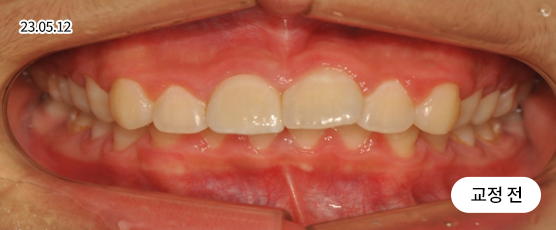

벌어진 치아교정 Solution

치아 벌어짐이 전체적으로 있는지 또는 부분(앞니 등)에만 있는지를 진단하고,

교정 장치를 부착하고 빈 공간으로 치아를 이동시켜 맞춰주는 방법으로 치료합니다.